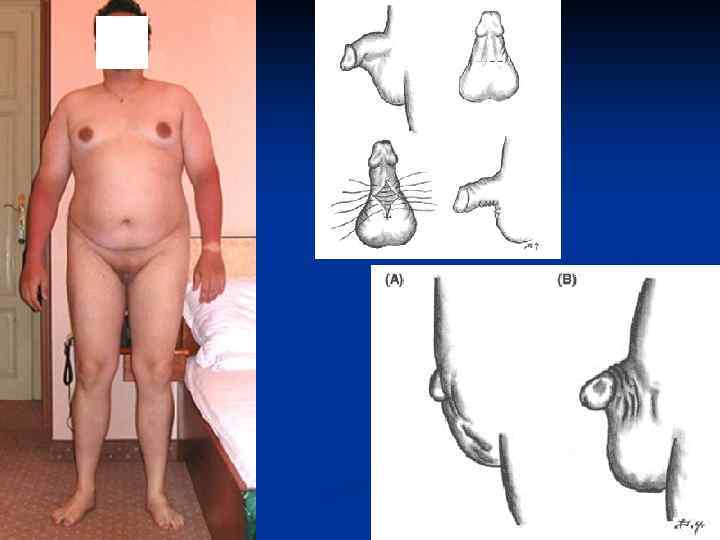

Аномалии структуры (гипоплазия) яичка. Гипоплазия яичка – это аномалия, при которой одно или оба яичка недоразвиты и уменьшены в размерах до 10 -15 мм. Двухстороннее недоразвитие яичек ведет к гормональной недостаточности и требует заместительной терапии тестостероном. Аномалии положения яичек (крипторхизм, эктопия яичка) - данная патология сопровождается нарушением нормального местоположения яичек за пределами мошонки. Крипторхизм - это часто встречающаяся аномалия яичек. При таком пороке одно или оба яичка не спускаются в мошонку во время внутриутробного развития ребенка. Яичко задерживается в брюшной полости или на уровне пахового канала. Частота такой аномалии развития яичек колеблется от 2 до 6% среди всех новорожденных мальчиков. У 9 -16% детей с крипторхизмом, особенно недоношенных, яичко опускается в мошонку в течение первого месяца жизни, на протяжении первого полугода еще у 29% детей яичко самостоятельно опускается в мошонку. По большей части наблюдается неопущение правого яичка, в 32 процентах левого яичка и в менее чем 22 процентах не опускаются оба яичка. Если оба яичка неопущены в мошонку и находятся в брюшной полости, у такого больного имеют место эндокринные нарушения, уровень тестостерона снижается. Мужские половые признаки развиваются недостаточно.

Аномалии структуры (гипоплазия) яичка. Гипоплазия яичка – это аномалия, при которой одно или оба яичка недоразвиты и уменьшены в размерах до 10 -15 мм. Двухстороннее недоразвитие яичек ведет к гормональной недостаточности и требует заместительной терапии тестостероном. Аномалии положения яичек (крипторхизм, эктопия яичка) - данная патология сопровождается нарушением нормального местоположения яичек за пределами мошонки. Крипторхизм - это часто встречающаяся аномалия яичек. При таком пороке одно или оба яичка не спускаются в мошонку во время внутриутробного развития ребенка. Яичко задерживается в брюшной полости или на уровне пахового канала. Частота такой аномалии развития яичек колеблется от 2 до 6% среди всех новорожденных мальчиков. У 9 -16% детей с крипторхизмом, особенно недоношенных, яичко опускается в мошонку в течение первого месяца жизни, на протяжении первого полугода еще у 29% детей яичко самостоятельно опускается в мошонку. По большей части наблюдается неопущение правого яичка, в 32 процентах левого яичка и в менее чем 22 процентах не опускаются оба яичка. Если оба яичка неопущены в мошонку и находятся в брюшной полости, у такого больного имеют место эндокринные нарушения, уровень тестостерона снижается. Мужские половые признаки развиваются недостаточно.